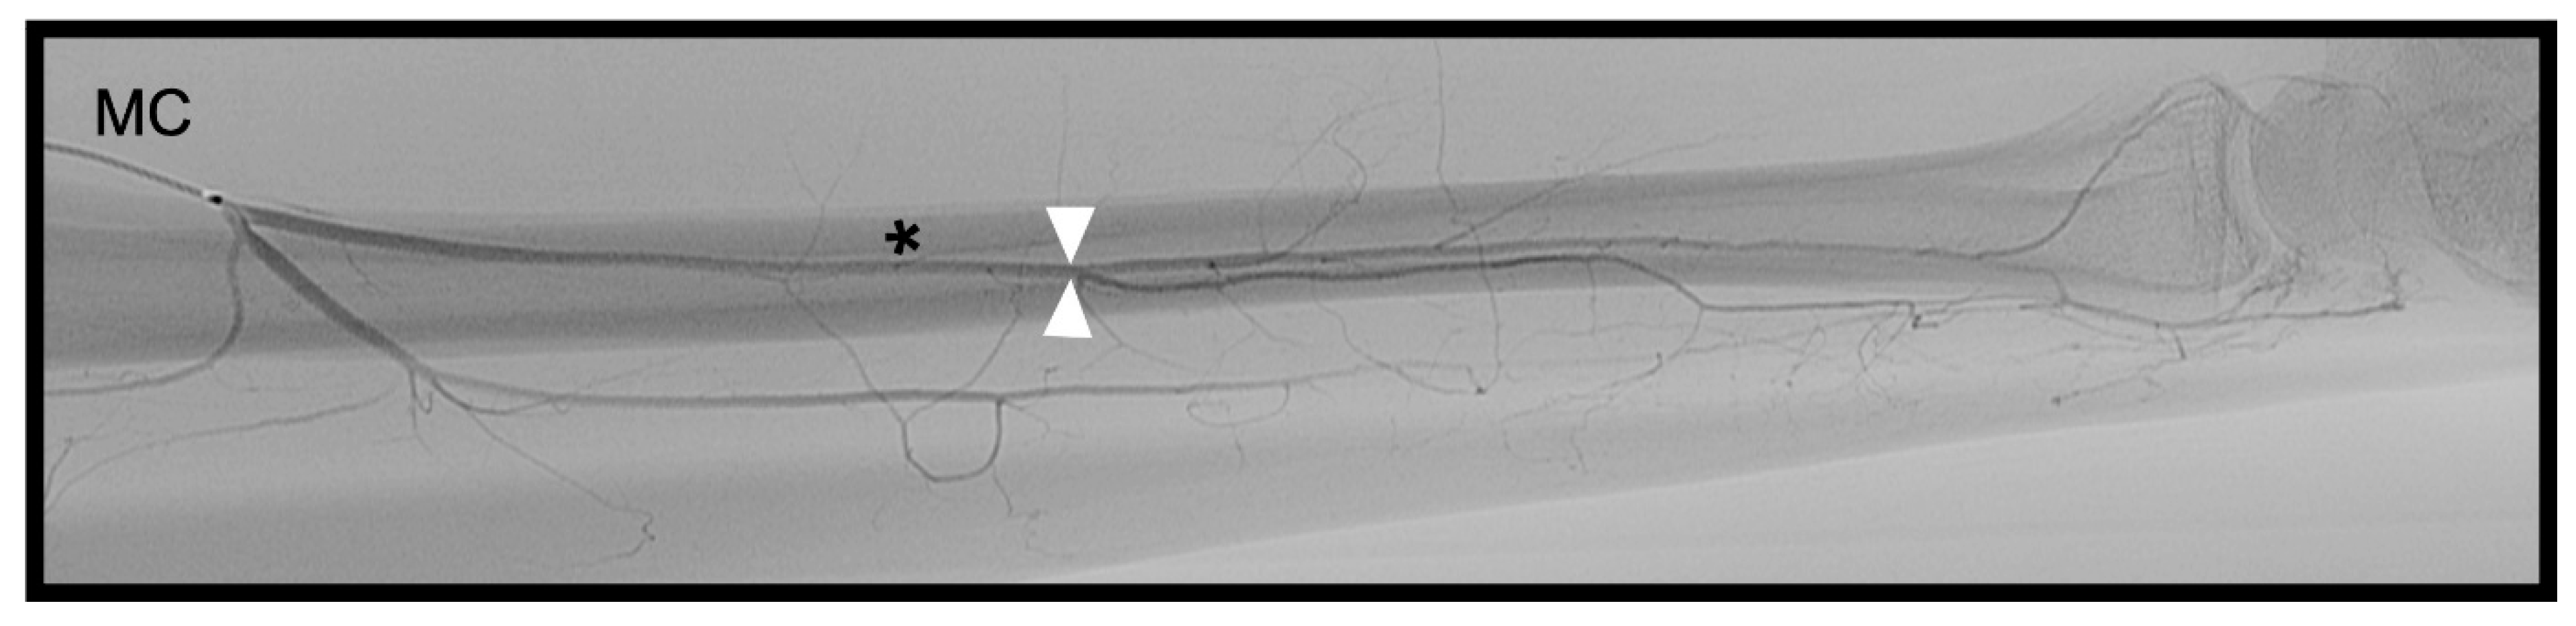

3.3. Anterior Interosseous Artery (AIA)

distance from the DCBUA to the styloid process of the ulnar (DCBUA = dorsal carpal branch of the ulnar artery).